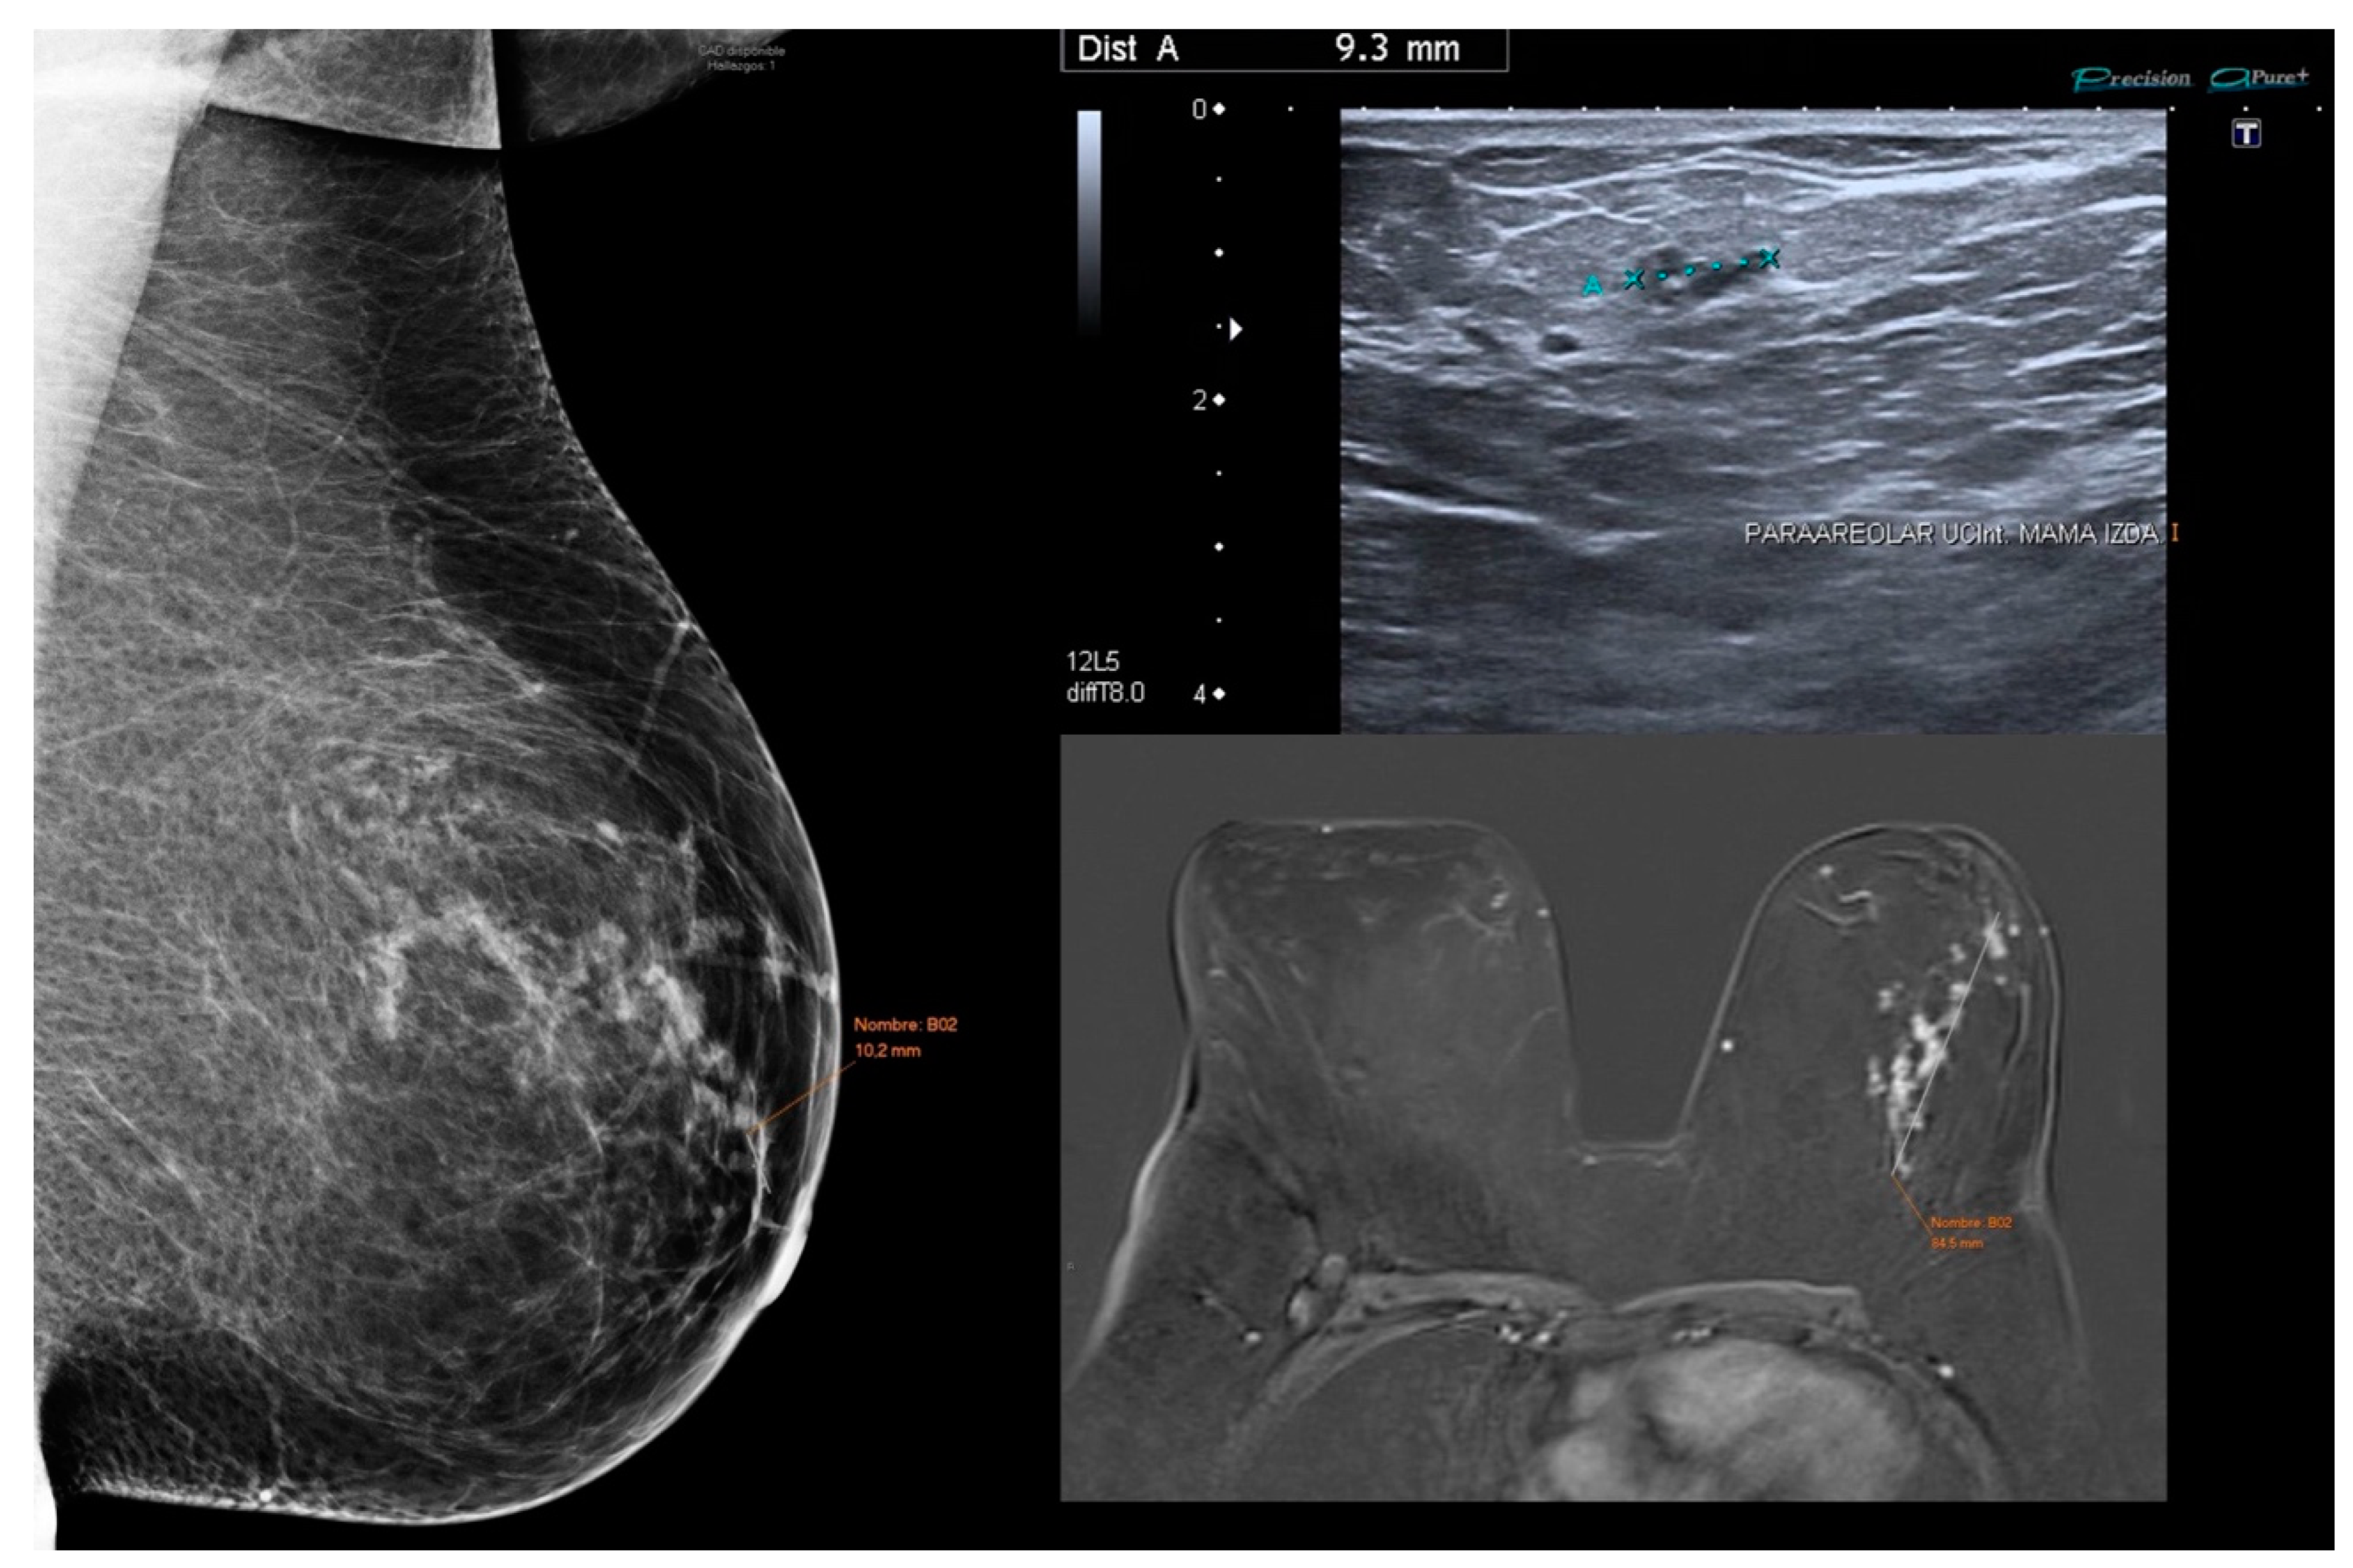

3.2. Mammographic Features

3.3. US Features

3.4. MRI Features

4.1. Mammography: Standard Technique with High Specificity

4.2. US: Complementary Method with Low Sensitivity in Pure DCIS

4.3. Radiologic-Histopathologic Findings

4.4. MRI Findings